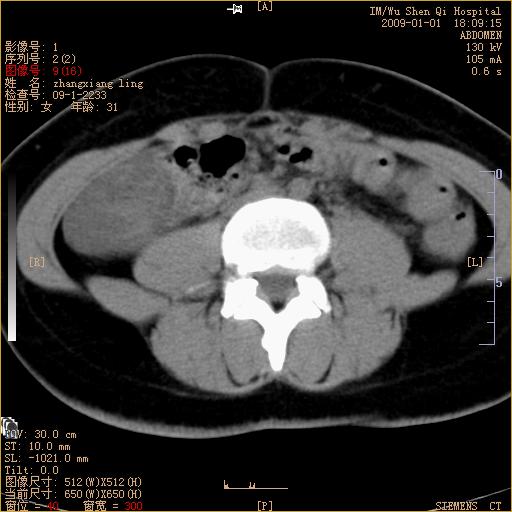

标题: CT17527:F31Y,腹痛伴血便9小时 [打印本页]

标题: CT17527:F31Y,腹痛伴血便9小时

升结肠肠壁不规则增厚,肠腔狭窄,考虑升结肠占位,建议增强扫描

升结肠肠壁不规则增厚,肠腔狭窄,考虑升结肠占位,建议增强扫描,不除外肠套叠.

升结肠肠壁不规则增厚,似呈同心圆改变,其有积液。结合病史首先考虑肠套叠伴肠壁坏死可能性大,结肠肿瘤待排。

患者已手术,结果肠系膜血栓形成肠坏死

结果:患者已手术,结果肠系膜血栓形成肠坏死。回过头再看局部肠壁增厚有分层(高密度坏死及低密度水肿)表现。